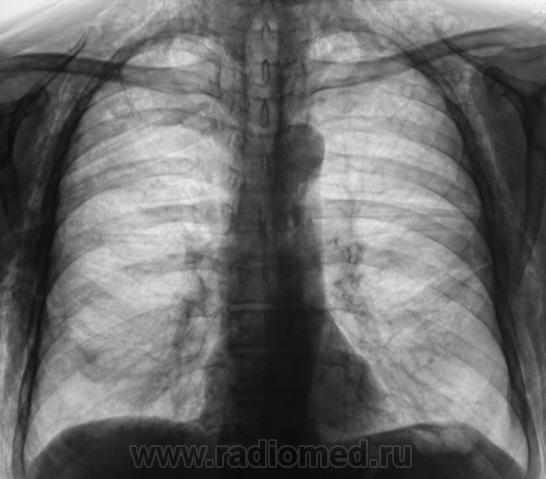

Шикарная эмфизема мягких тканей, перелом 8 -го ребра справа по задней подмышечной линии (как минимум)....

Этого пациента, сегодня дали на контроль. Первичная рентгенограмма от 8.05., там плюсом, имело место коллабирование правого легкого на 2/3.